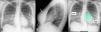

False positive AI results due to breast implants on chest radiographs: The importance of the lateral view

Resultados falsos positivos de la IA debido a prótesis mamarias en la radiografía de tórax: la importancia de la proyección lateral